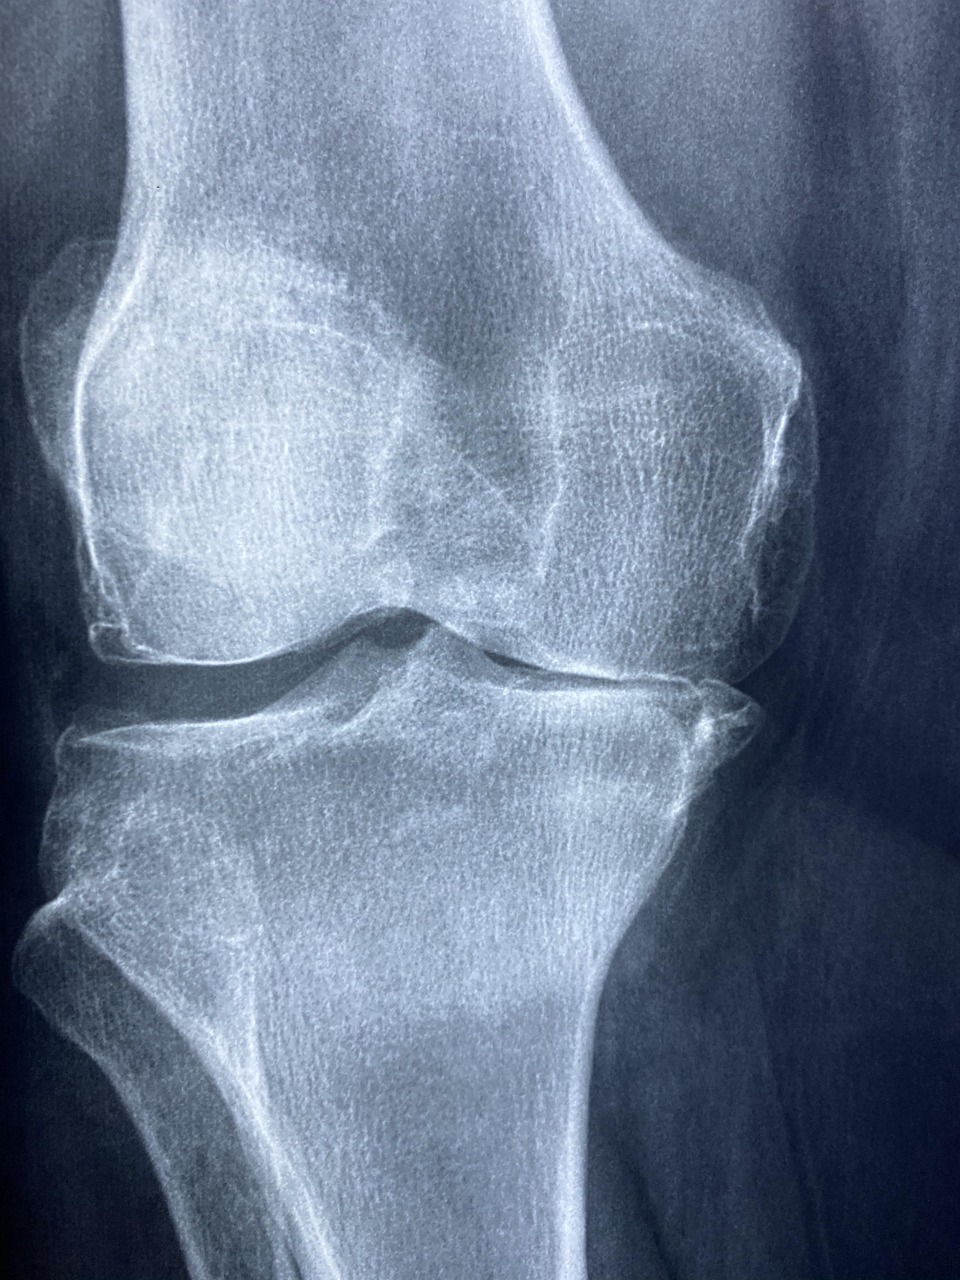

– Diagnostik mit bildgebenden Verfahren (z. B. Röntgen, MRT, Ultraschall)